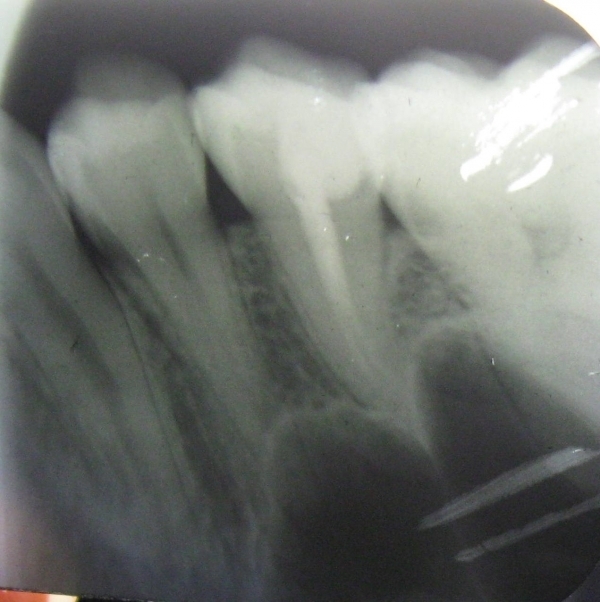

В середине ноября у меня разболелся зуб - верхняя правая 5-ка. Боль тупая, ноющая, иногда с ощущением распирания. Поставили диагноз пульпит, удалили нерв. Но после лечения оставалась легкая боль при накусывании, в январе зуб начал также реагировать на перкуссию. Я посетила консультацию у другого врача, сделала рентген. Мне сказали, что зуб запломбирован нормально, это может быть просто реакция организма на переохлаждение. Со времени той консультации прошел месяц, боль не ушла, зуб стал реагировать на горячее ощущением распирания. Еще иногда я замечаю неприятный привкус, идущий из пространства между этой 5-кой и 6-ой, как будто там что-то гниет.

На мой взгляд, зуб пролечен хорошо, но для полной картины и оценки необходим К/Т (трехмерный снимок). Все симптомы говорят о периодонтите.